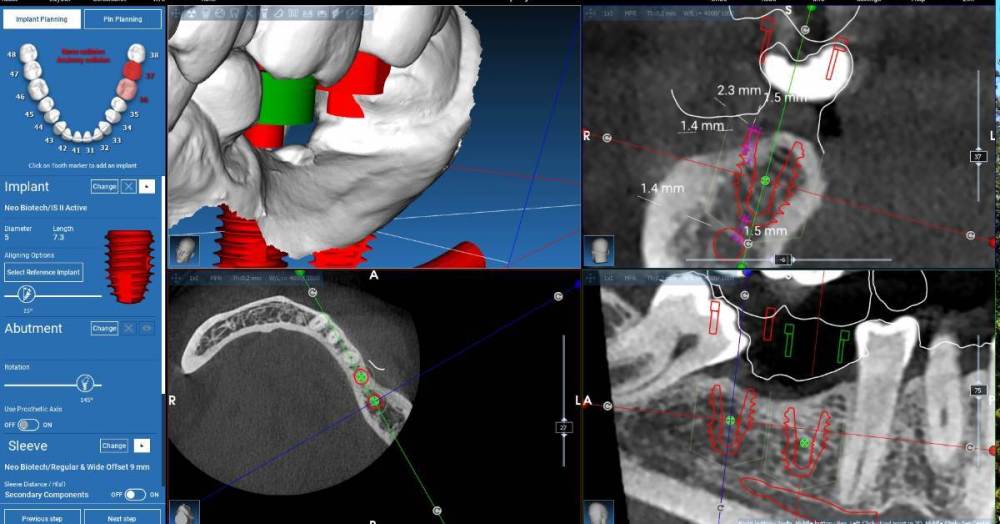

Fin Опубликовано 21 августа, 2023 Поделиться Опубликовано 21 августа, 2023 Здравствуйте коллеги. Появился такой клинический случай. Как вы считаете поможет ли установка 2 импл. штрауман 4.1 на 6 с полированной шейкой 1.8 в данной ситуации? На скриншотах представлен необиотек это как второй вариант 4.6 -4х 7.3 с полировкой 0,5 и 4.7- 5х7.3 с полировкой 1.3 . Штрауман будет на 0,5 мм выше коронально. Спасибо Ссылка на комментарий

Fin Опубликовано 21 августа, 2023 Автор Поделиться Опубликовано 21 августа, 2023 (изменено) 1 час назад, koreandr сказал: В дистальный вроде как WN 6 мм войдет. Спасибо.Вы имеете ввиду диаметр 4.8? Я в Штрауманах плоховато разбираюсь, но для таких клин случаев нужно. 1 час назад, stommm сказал: Как вариант оба 5х7.3. У 46 шейку повыше. И 47 лучше вестибулярнее. Дефицит десны язычно потом намного сложнее решить будет. Благодарю. Оба Необиотека 5x7.3 с полировкой 1.3? Изменено 21 августа, 2023 пользователем Fin Ссылка на комментарий

stommm Опубликовано 21 августа, 2023 Поделиться Опубликовано 21 августа, 2023 15 минут назад, TIGER сказал: Для нео 7.3 кости надо 10 мм для заглуба Зачем если шейка 2.3? Ну и судя по скринам влезает по высоте точно. Но тут коронок не видно. Выглядит будто 47 в перекрес выйдёт. Штрауманн тоже можно. Дистально 6 мм. Медиально 6 или 8 (рисовать с учётом коронки и выбирать) Ссылка на комментарий